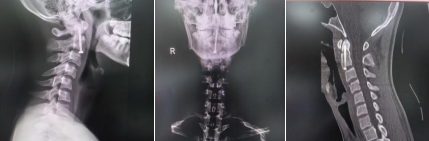

患者杨某因摔伤出现颈背部疼痛、活动受限,于受伤1小时余急诊入院。经影像学检查及专科评估,确诊为“颈枢椎齿状突基底骨折”。该骨折部位具有较高风险——枢椎齿状突紧邻延髓(生命中枢相关结构),若发生骨折移位,可能压迫延髓引发危急情况,需尽快制定安全的治疗方案。 ▲术前CT及MRI 针对患者的病情,脊柱外科主任柯绍强第一时间组织科室核心成员开展病例讨论。结合患者年龄特点,团队最终确定采用“经皮前路枢椎齿状突骨折切开复位空心钉内固定微创手术”。该术式虽具有出血少、创伤小、术后恢复周期相对较短的特点,但操作难度较高:颈枢椎周围分布食道、气管、颈总动静脉等重要解剖结构,且需固定的枢椎齿状突体积较小,穿刺针的角度、深度若出现偏差,可能损伤周边重要神经血管,存在一定风险。 为保障手术安全,脊柱外科团队术前反复推演手术流程、完善应急预案,并邀请中山大学孙逸仙纪念医院脊柱外科专家唐勇教授到场指导。手术过程中,医护团队密切配合,精准操作,成功避开周围重要组织,顺利完成骨折复位与内固定操作,术中患者生命体征保持平稳。 术后检查显示,患者四肢功能未出现异常,无发生相关并发症。术后第一天,患者在佩戴颈托的情况下可下床活动;术后7天经综合评估符合出院标准,予以办理出院手续。 ▲术后DR及CT ▲手术切口 医生提醒 颈椎是人体重要的支撑部位,青少年活泼好动,日常运动或意外摔倒时需注意保护颈部。若出现颈部疼痛、活动困难等情况,切勿自行按摩或随意转动头部,应立即就医检查,避免因延误治疗导致病情加重。 此次案例也提示,面对颈椎损伤等复杂伤情,需通过专业评估制定科学方案,规范的诊疗流程和团队协作是保障治疗效果的关键。 脊柱外科 基本概况 我院脊柱外科是阳江市“十四五”临床重点建设专科,开放床位35张,专注脊柱疾病临床研究与治疗。科室拥有16名专业医护人员,并与省内知名三甲医院建立长期合作关系,定期开展学术交流与远程会诊,确保患者在阳春本地就能享受到省级优质的脊柱疾病诊疗服务。 诊疗技术 科室配备超声骨密度仪、C臂X光机、德国Maroresn脊柱内窥镜等尖端设备,为精准诊疗提供坚实技术保障。 科室可独立开展六大核心技术: ▷上颈椎骨折脱位椎弓根钉内固定术 ▷颈椎前后路联合入路复杂手术 ▷多节段胸腰椎骨折修复术 ▷胸腰椎结核病灶清除+植骨融合术 ▷椎管肿瘤显微切除术 ▷退行性脊柱侧弯三维矫形术 微创技术是科室一大亮点,涵盖胸腰椎压缩性骨折经皮成形术、脊柱骨折微创内固定、椎间孔镜下椎间盘髓核摘除等前沿术式,以小创口实现大疗效,显著缩短患者康复周期。 科室坚持中西医并重,传承中医特色疗法,开展针灸、中药包外敷、穴位按摩、肢体康复锻炼等项目,为患者定制个性化综合治疗方案,让传统医学智慧赋能现代脊柱诊疗。 专家简介 唐 勇 医学博士,中山大学孙逸仙纪念医院脊柱外科副教授,硕士研究生导师,脊柱微创中心副主任。 专业特长:曾到美国加州大学脊柱中心留学进修。擅长脊柱外科研究,能熟练掌握脊柱外科高难度手术以及疑难病症的诊治。2010年开展世界首例单孔腔镜下腰椎前外侧手术治疗腰椎结核。2016年开展我国第一例达芬奇机器人脊柱手术。我国第一位获得达芬奇机器人操作许可证的骨科医生。 学术任职:担任中华医学会骨科分会微创学组全国委员、广东省医师协会脊柱内镜学组副组长。《脊柱内镜手术策略及操作图谱》主编。The International Journal of Neuroscience,The Journal of Rheumatology,Global spine journal 国际杂志审稿专家。 陆晓生 主任医师、党委副书记、院长、研究员、医学博士,硕士、博士研究生导师。 历任百色市妇幼保健院(副处)、百色市人民医院、北流市人民医院、新乡医学院第三附属医院(第三临床学院)院长(正处)。武汉大学硕士、广西医科大学博士毕业,深造于北京积水潭医院、匈牙利德布勒森大学等。 科研成果: 以第一作者发表专业论文20余篇(含SCI收录);获7项国家专利授权;主持科研项目获奖6项,其中1项获省部级科研立项资助和省部级科技进步奖,实现了百色市本级医疗系统在该领域的零突破。 学术任职: 现兼职任中国人体科技健康促进会现代医院精益管理专业委员会常委,曾兼任中国中西医结合学会骨伤科分会第八届委员会骨搬移治疗糖尿病足及微血管网再生专家工作委员会常委、广西医师协会骨科医师分会外固定专业委员会副主任委员、广西医院协会县级医院管理分会副主任委员、广西医师协会第一届创面修复与再生专业委员会副主任委员等专业学术职务。 荣誉奖项: 广西第一批高层次人才E层次、广西“十百千”第二层次人选、广西先进工作者(广西五一劳动奖章)等;百色市第七、八批专业技术拔尖人才;玉林市高层次人才第三、第四层次人选;荣获第六届“县域医疗榜样力量”系列评选奖优秀院长奖。 擅长领域: 熟悉骨科专业,擅长骨关节、创伤、脊柱基础和临床研究及骨科新器械研发及应用研究。对医院管理有丰富经验。 柯绍强 骨外科主任医师,脊柱外科主任。 毕业于广东医科大学临床医学专业,曾先后到广东省人民医院、中山大学附属医院脊柱外科及脊柱微创中心进修学习。曾发表多篇省及国家级医学论文,主持完成阳江市科研项目2项,广东省医学教育协会脊柱专业委员会常务委员、广东省基层医药学会脊柱专业委员会常务委员、广东省健康管理学会脊柱专业委员会委员、广东省康复医学会脊柱脊髓分会理事、阳江市医学会骨科分会副主任委员、阳江市医学会脊柱专业委员会常务委员。 擅长领域:熟练掌握脊柱外科高难度手术,率先在阳江地区开展经皮椎体成形术、经皮椎弓根钉内固定术、微创通道下腰椎融合内固定术及经椎间孔镜下椎间盘髓核摘除椎管减压等脊柱微创手术。擅长颈椎病、颈腰椎间盘突出、腰椎管狭窄、腰椎滑脱、胸腰椎骨质疏松性压缩性骨折、脊柱感染脊柱结核、脊柱脊髓损伤、脊柱畸形、脊柱肿瘤等疾病的诊治以及脊柱微创手术。 刘丙科 骨外科副主任医师,脊柱外科副主任。 毕业于广东医科大学,曾先后到中山大学附属第一医院脊柱外科、中山大学附属孙逸仙纪念医院脊柱微创中心进修学习。发表专业论文7篇,主持完成阳江市科研立项2项。广东省医院协会脊柱外科专业委员会第一届委员、广东省健康管理学会脊柱专业委员会第一届青年委员会、广东省基础医药学会骨科修复重建专业委员会第一届委员、广东省中西医结合学会骨科微创专业委员会第三届委员会委员、广东省医疗行业协会脊柱外科管理分会委员、广东精准医学应用学会脊柱脊髓病分会第一届委员、阳江市医学会脊柱外科学分会第一届委员会委员。 擅长领域:对脊柱各类疑难疾病诊治有丰富的临床经验,擅长颈胸腰椎管减压、椎间盘切除、椎体滑脱或骨折复位、椎间植骨融合、椎体病灶清除、椎弓根螺钉内固定术等传统手术,并擅长经皮椎体成形术(PVP)、经皮椎体后凸成形术(PKP)、选择性神经根阻滞术、脊柱内镜辅助下髓核摘除术、射频消融术等微创技术。 洪锦向 骨外科副主任医师。 毕业于广东医科大学临床医学专业,从事骨科工作10多年,曾先后到广州医科大学附属二院、广州医科大学附属一院骨外科进修学习。曾发表省及国家级论文7篇。 擅长领域:熟练掌握脊柱疾病、关节疾病、骨病、四肢骨折、创伤等常见病及疑难病的诊治,尤擅长脊柱各类疾病诊治及手术治疗。 胡海生 骨外科主治医师,脊柱外科硕士研究生。 研究生期间于南方战区总医院(原广州军区总医院)跟随马向阳教授、夏虹院长、吴增晖副院长等国内知名脊柱外科教授学习三年。曾在国内及国外杂志发表学术论文5篇,研究生毕业后主要从事脊柱外科临床工作。 擅长领域:对颈椎病、颈椎管狭窄症、寰枢椎脱位、脊髓损伤、脊柱骨折、腰椎间盘突出症、腰椎滑脱症、腰椎管狭窄症、骨质疏松性椎体压缩性骨折等脊柱疾病的诊断与治疗有较深入研究。